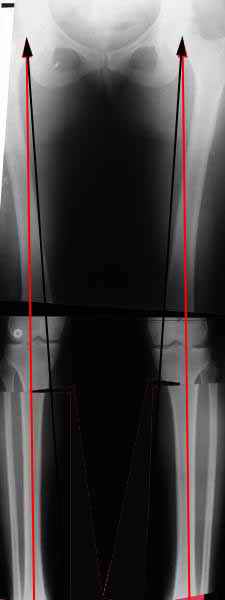

Вот, с учетом и без учета, и на разных уровнях...

a> Из приведнной схемы не совсеим понял что означают разноцветные линии.

Черные - это нынешняя механическая ось. Красные - это планируемая правильная ось.

a> И зачем латерализация периферического фрагмента.

;-) Читайте Палея. Стр. 114-115.

a> Я всегда делаю медиализацию. См схему. И для данного случая

Медиализация - это чисто эстетический прием, как я понимаю. Поскольку если делать остеотомию ниже вершины деформации, для восстановления оси надо делать смещение по ширине, в данном случае как раз латерализацию.

А вот на схемке без осей - там на разных уровнях (который правильнее?) устранение варуса чисто открытым клином без медиализации-латерализации. Если как-то так сделать - этого недостаточно будет?